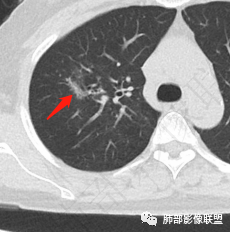

影像特点:右肺上叶混合磨玻璃影,边界清晰,结构松散,内有多结节堆积及支气管扩张影,可见小叶间隔增厚,并局部增厚的小叶间隔上亦存在微结节,胸膜侧可见纤细索条,病灶周围可见多发微结节影。

总体分析:从病灶分布来看符合结核的好发位置,影像表现也符合结核的多态性,且出现卫星灶。由于有边界清晰的GGO,需要鉴别腺癌,虽然此病例有边界清晰的GGO,但是它的GGO的边缘有结节感,呈多结节堆积,而腺癌的GGO缺乏这种“多结节堆积感”,另外,此病例也没有发现腺癌的胸膜凹陷征、毛刺征及月牙铲等。

1、年轻人多见,一般提示免疫力可能有下降。 2、好发部位与其它结核类似,上叶及下叶背段为主。 3、烟花征,反晕征,环呈结节状,可以伴随空洞,树芽征,结节灶,胸水。(反晕征:一般周围实性环形高密度影,中央丛密度低;一般环超过圆的3/4,结核的环主要是小叶核心结节组成,类似于多发树芽征聚集,边缘结节感。中央的晕:可以是腺泡结节,树芽征,细网状,磨玻璃影,很少正常,主要成分是小叶内间质增厚、小叶核心结节、肺泡内病变。)其实也体现了结核的多灶性、多态性特点。

4、其实不一定完全表现为反晕征,还有比较密集的烟花,聚集成团,与反晕征同在。